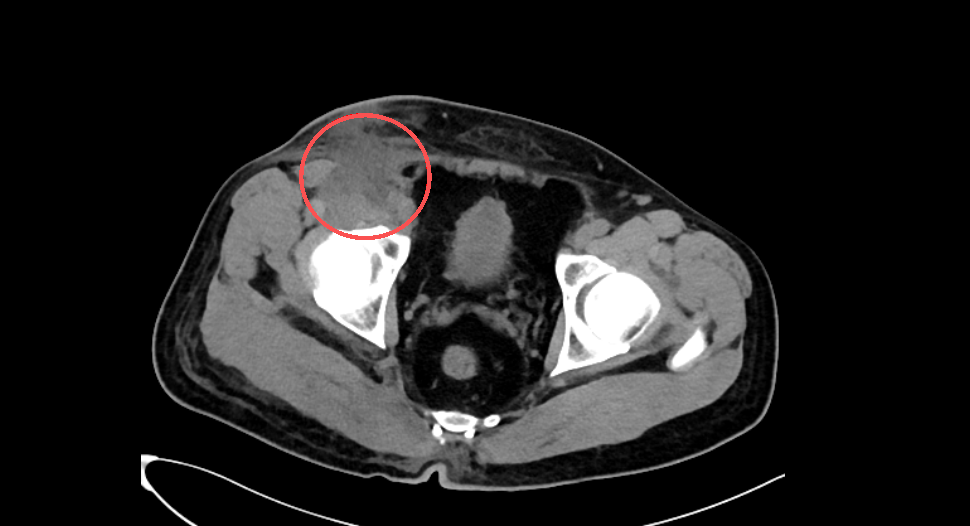

术前ct照

患者徐先生工作时被机械挤压致臀部、右侧腹股沟等多部位开放性伤口伴出血,伤后10天因症状未缓解入院。查体见患处广泛淤青,存在潜行窦道、大量坏死组织,极易引发严重并发症,救治与修复难度极大。

针对患者的复杂伤情,创面修复与烧伤科团队迅速组织病例讨论,制定阶梯式、个性化的综合治疗方案,决定为患者实施腔镜下右侧腹股沟血管探查、清创+创面封闭负压引流术,借助腔镜微创技术精准探查,精准清除坏死组织与炎性病灶,为创面愈合创造良好基底。术后7天团队再次开展右侧腹股沟扩创探查+创面封闭负压引流术,进行二次精细化彻底清创处理,优化愈合环境。针对后期创面愈合不佳及软组织缺损问题,团队为患者实施腹股沟筋膜组织瓣修复术,通过筋膜组织瓣转移精准填补缺损,重建腹股沟区域的完整性,并实现腹股沟区域外观和功能的统一性,解决了复杂创面难以闭合的关键问题。